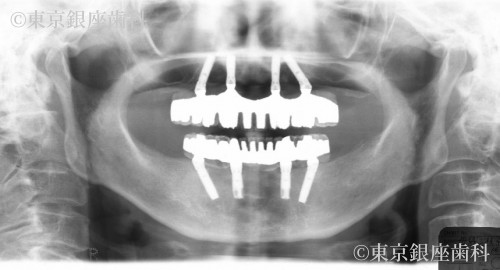

歯周病とむし歯によって咬合崩壊 上下ワンデイインプラントにて再構築した症例

Before

症状の経過と現在の状態

痛みが出たり不具合があればその都度費用もかけて治療。しかし歯科医院の転院を繰り返していて定期健診等は受けていなかった。

歯周病の進行で歯に動揺があり長期の保存が難しく、臼歯の欠損で咬み合わせが下がって前歯部への負担が大きくなっているため全顎的な治療が必要と判断。最小限のインプラント埋入によって咬合を回復させるため上下ワンデイインプラント処置を計画。